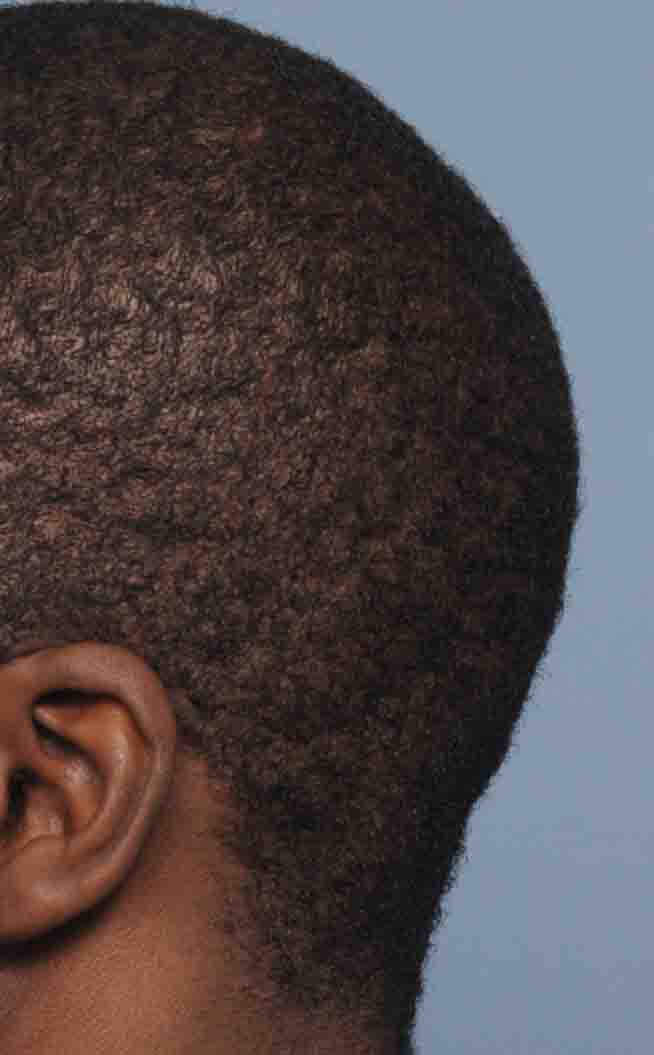

Patient 1

Desire for removal of occipital knob on back of skull.

Occipital knob skull reduction done through a small 3cm overlying skin incision.